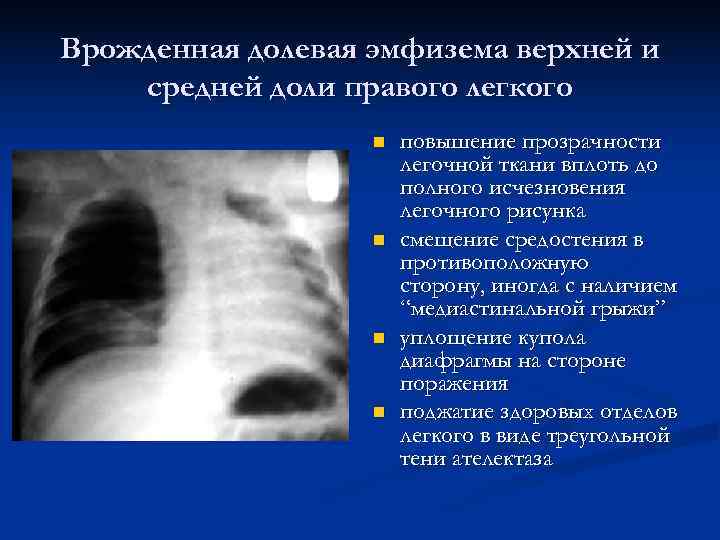

Рентгеновские снимки при врожденной эмфиземе легкого

Раздел: Визуальные уроки